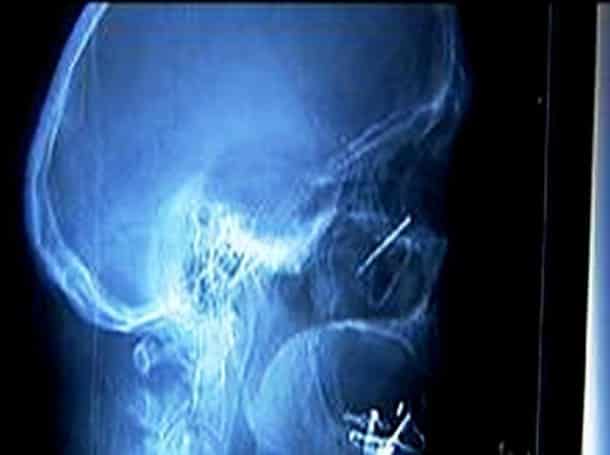

33 radiographies qui prouvent que les gens font des choses douteuses avec leur corps !